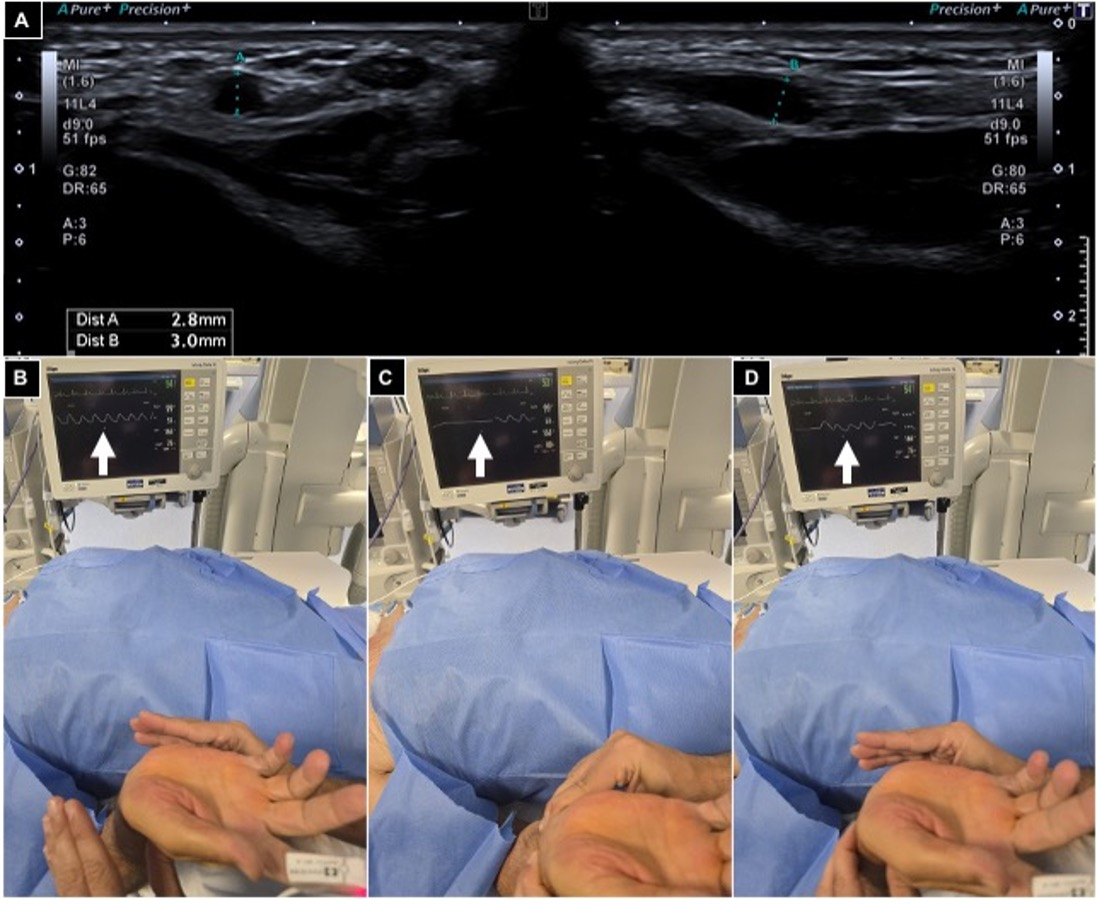

2.4. Procedures